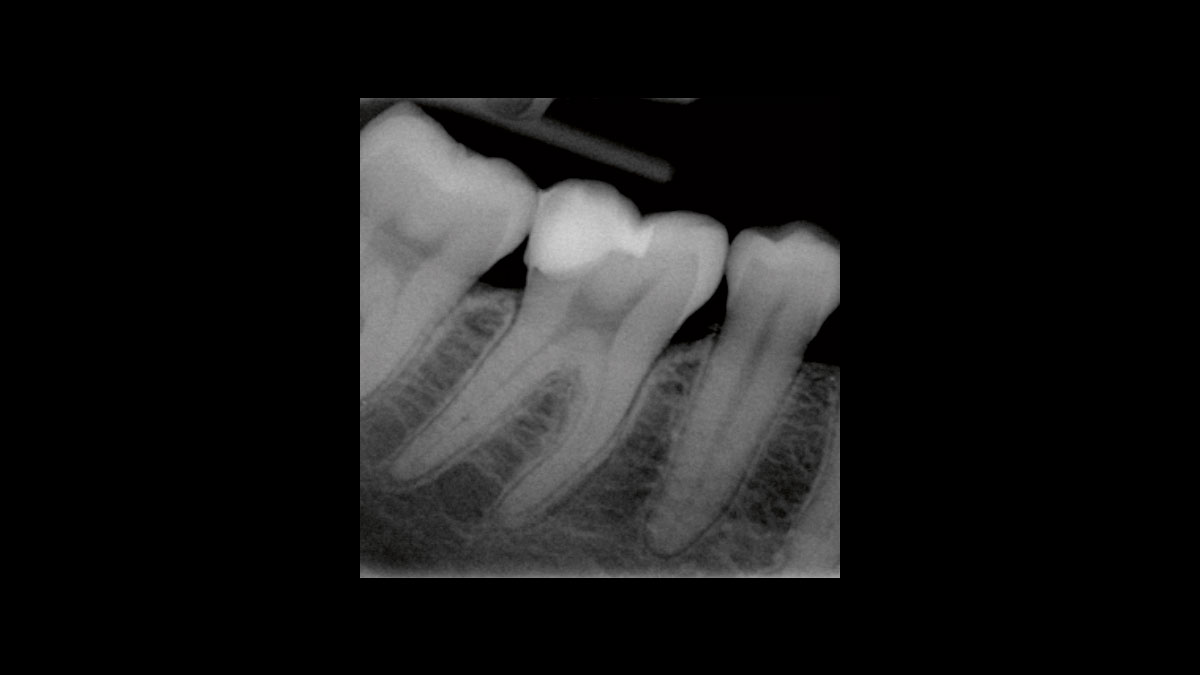

• Reducción de bacterias en procedimientos endodónticos

Reducción de bacterias en procedimientos endodónticos